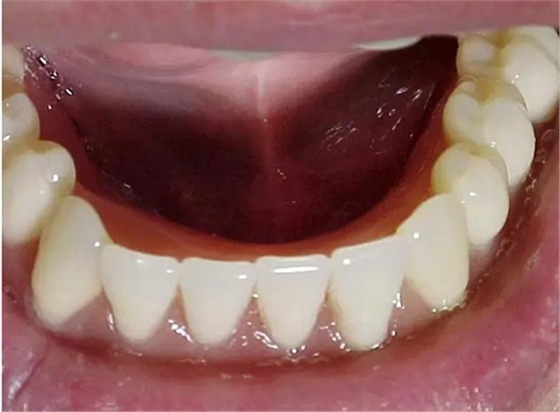

醫(yī)生在為患者制取印模之前,必須先對患者口腔的內(nèi)外環(huán)境進(jìn)行一個(gè)系統(tǒng)的檢查,包括患者現(xiàn)有的義齒、牙槽嵴的情況、粘膜的情況、唇頰舌肌和舌體情況、顳下頜關(guān) 節(jié)的情況等等。通過觀察,醫(yī)生要明確印模的輪廓,未來基托以及牙列的輪廓。并且要在義齒設(shè)計(jì)單上標(biāo)注有關(guān)的信息,讓技師的操作更明朗化。

尤其是口內(nèi)的檢查,應(yīng)當(dāng)仔細(xì)的檢查和觸診,對技師確定基托的范圍和厚度、需要緩沖和伸展的區(qū)域做明確的描述。

特別是有些牙槽嵴吸收嚴(yán)重的患者,此時(shí)患者的前庭顯得相當(dāng)?shù)膶?,醫(yī)生應(yīng)當(dāng)記錄下見到的情景,讓技師在操作時(shí)做到心中有數(shù)。

還可以通過照片的形式,讓技師直觀地了解患者有關(guān)的信息。